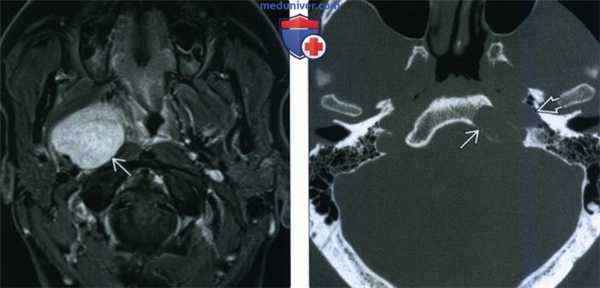

МРТ. шваннома преддверно-улиткового нерва у пациента с левосторонней потерей слуха. На Т2-взвешенном изображении (а) определяется опухоль мостомозжечкового угла, изоинтенсивная по отношению к ткани головного мозга. Мелкий узловой компонент опухоли в просвете слухового прохода более четко определяется на Т1-взвешенном изображении (b) с усилением после введения гадолиния.